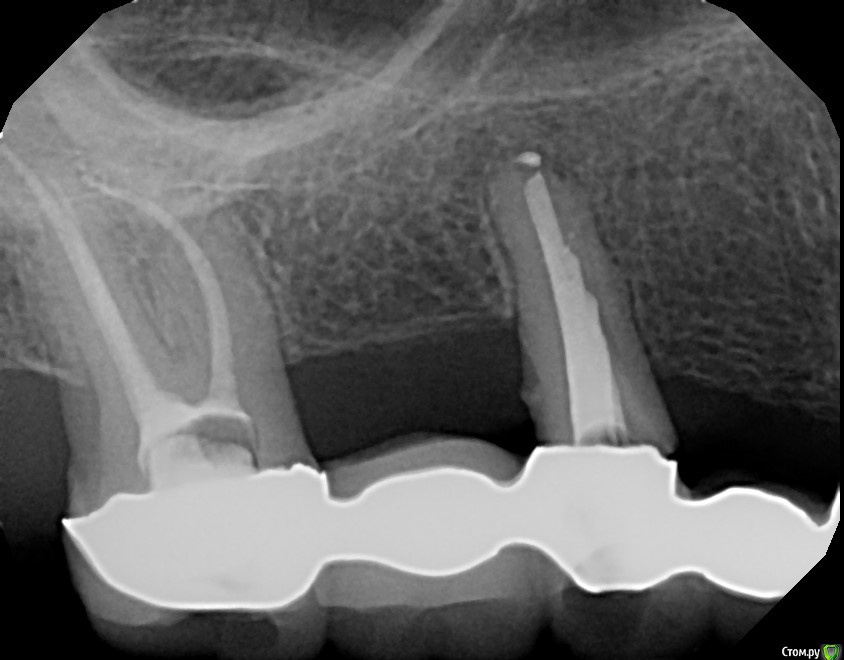

Dirina12 Опубликовано 11 июля, 2017 Автор Поделиться Опубликовано 11 июля, 2017 Здесь ( зуб номер 2) тоже видно что 2 канала запломбировано, а 3-го нет. Как так? Ссылка на комментарий

Ponchik Опубликовано 12 июля, 2017 Поделиться Опубликовано 12 июля, 2017 2 канала запломбировано, а 3-го нет. Третий есть. Внимательнее посмотрите. Вот есть ли четвертый не видно. а 3-й не мог найти (делал со снимками и микроскопом). Вот если бы не сказал и залепил, "как есть" - тогда плохой. И почему не мог найти ? Этот вопрос надо задать вашему зубу - почему каналы не в типичном месте? Почему облитерированы? Если нет доверия к врачу и Вы ищите ошибки в каждом его действии - меняйте врача. Ссылка на комментарий

Dirina12 Опубликовано 12 июля, 2017 Автор Поделиться Опубликовано 12 июля, 2017 Если нет доверия к врачу и Вы ищите ошибки в каждом его действии - меняйте врача. Врач сказал,что проблема в том что зуб был леченый много лет назад (лет 25 назад в Украине) и они использовали материал для пломбирования каналов ,что во-первых его не видно на снимке, а во-вторых его очень трудно извлечь из канала. Сейчас я лечусь в США и ето амер. доктор. Он намучился с другим зубом, чтобы извлечь етот материал из канала и перелечить его. Я считаю его хорошим доктором и он мне нравится. Он перелечил мне зуб номер 2 и он утих, хотя год назад тоже амер. доктор его лечил и он все еще ныл. Поетому я поменяла его на теперешнего. Спросила, потому что не хочу разочаровываться в нем, т.к. очень трудно найти хорошего дантиста даже здесь в Америке. У всех только долары в глазах, а помощи никакой. Мне еще предстоит с етим доктором резекция и пломбирование через десну зуба номер 7, поетому волнуюсь. Т.е. вы допускаете,что не всегда можно найти все каналы и ето не зависит от квалификазии доктора? Ссылка на комментарий

red_butler Опубликовано 13 июля, 2017 Поделиться Опубликовано 13 июля, 2017 А что ето меняет? По-другому лечился бы? Или что?Так, здесь(в США) делают, наверное потому что новая коронка будет стоить $1,5К. Пломбирование канала $1,6К. Вот и считайте 1 зуб стоит больше $3К.Это меняет всё.Это усложняет лечение. Коронки после лечения все равно требуют замены. Нет понимания о состоянии опорных зубов, и следовательно лечение может быть напрасным.На снимке вижу как минимум один зуб с сомнительным прогнозом. Ссылка на комментарий